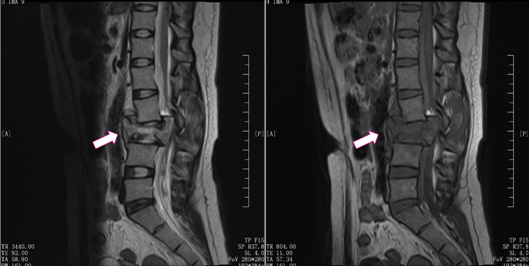

骨科张海龙主任对小郑进行了全面的体格检查,评估了脊柱四肢的运动、感觉和神经反射等情况,并加做了腰椎核磁共振检查。根据影像检查和其他检查结果,发现小郑是腰3椎体爆裂性骨折的骨折碎块压迫脊髓,引起双下肢的不完全性瘫痪,并且合并有马尾神经损伤。

腰椎MRI显示

在完成了必要的术前检查之后,张海龙主任经过全面的评估和慎重的考虑,为小郑进行了“腰椎后路减压+L1、L2、L4、L5椎弓根螺钉内固定+侧路人工椎体内固定术”。可伸缩的人工椎体在微创通道下放置到骨折节段,手术切口仅有5cm左右。